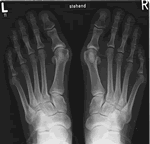

Fotos Dedos Hallux

Hallux Valgus Hallux Valgus Hallux Valgus Hallux Valgus